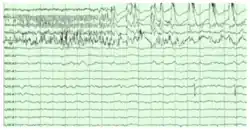

William Skaggs, public domain

The hippocampus shows two major "modes" of activity, each associated with a distinct pattern of neural population activity and waves of electrical activity as measured by an electroencephalogram (EEG). These modes are named after the EEG patterns associated with them: theta and large irregular activity (LIA). The main characteristics described below are for the rat, which is the animal most extensively studied.[67]

The theta mode appears during states of active, alert behavior (especially locomotion), and also during REM (dreaming) sleep.[68] In the theta mode, the EEG is dominated by large regular waves with a frequency range of 6 to 9 Hz, and the main groups of hippocampal neurons (pyramidal cells and granule cells) show sparse population activity, which means that in any short time interval, the great majority of cells are silent, while the small remaining fraction fire at relatively high rates, up to 50 spikes in one second for the most active of them. An active cell typically stays active for half a second to a few seconds. As the rat behaves, the active cells fall silent and new cells become active, but the overall percentage of active cells remains more or less constant. In many situations, cell activity is determined largely by the spatial location of the animal, but other behavioral variables also clearly influence it.

The LIA mode appears during slow-wave (non-dreaming) sleep, and also during states of waking immobility such as resting or eating.[68] In the LIA mode, the EEG is dominated by sharp waves that are randomly timed large deflections of the EEG signal lasting for 25–50 milliseconds. Sharp waves are frequently generated in sets, with sets containing up to 5 or more individual sharp waves and lasting up to 500 ms. The spiking activity of neurons within the hippocampus is highly correlated with sharp wave activity. Most neurons decrease their firing rate between sharp waves; however, during a sharp wave, there is a dramatic increase of firing rate in up to 10% of the hippocampal population